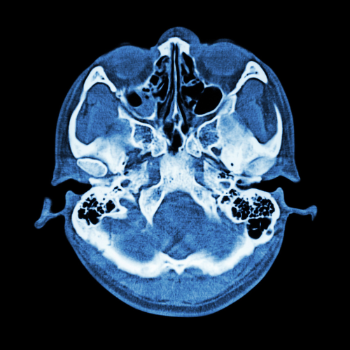

Maya Sharma, a 45-year-old school teacher from Pune, is known for her unwavering dedication to her students and her family. However, Maya's life took a drastic turn when she started experiencing frequent headaches, vision problems, and a persistent ringing in her ears. After numerous consultations and tests, Maya was diagnosed with a skull base tumor, a daunting revelation that left her and her family in despair.

For Maya, the diagnosis was more than just a medical condition; it was an emotional rollercoaster. The thought of undergoing surgery was terrifying, and the potential risks and complications weighed heavily on her mind. The fear of losing her ability to teach, to see her students, and to be there for her family was overwhelming. This is where Dr. Jayant Gaud's expertise in skull base surgery comes into play.

The surgery was a success, and Maya's recovery was carefully monitored by Dr. Gaud and his dedicated team. Today, Maya is back in her classroom, inspiring her students with her resilience and courage. Her vision is restored, the headaches are gone, and the ringing in her ears is a thing of the past. For Maya, skull base surgery was not just a medical procedure; it was a life-changing event that restored her hope and happiness.